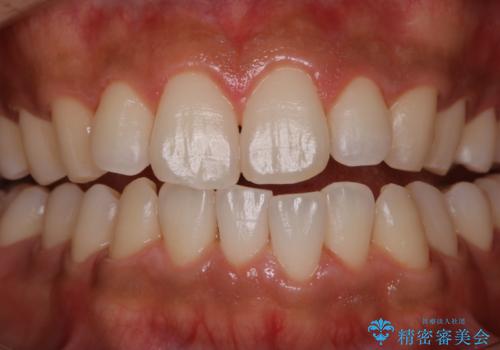

- 特に症状など気になるところはないが、メンテナンスして欲しいとのことでした。染め出しをしてのブラッシング指導とPMTC30分コースを行いました。

磨き残しが多くなると、お口の健康を維持していくのが難しくなってしまいます。お口の健康を守っていくためには、毎日のハミガキを行っていくのが基本です。そのため、なにか症状がなくても定期的に歯科医院で口の健康状態のチェックをすることが大切です。